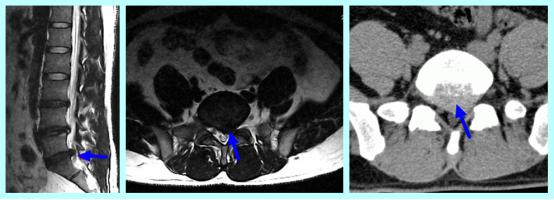

唐都医院脊柱神经外科王鹏教授结合患者病史、体征、症状及影像资料确诊患者为腰5骶1椎间盘突出,且突出造成明显的左侧神经根压迫,患者手术指征明确,建议手术治疗。